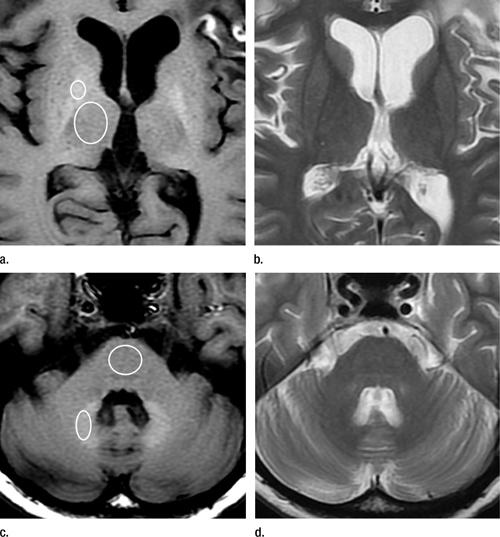

Figure 1. MR images in 45-year-old woman with glioblastoma treated with surgery, chemotherapy, and radiation therapy. (a) Unenhanced T1-weighted image shows high-signal-intensity globus pallidus. Standard ROIs were placed around globus pallidus and thalamus. (b) Fast spin-echo T2-weighted image at same level as a. (c) Unenhanced T1-weighted image shows high-signal-intensity dentate nucleus. Standard ROIs were placed around dentate nucleus and pons. (d) Fast spin-echo T2-weighted image at same level as c.